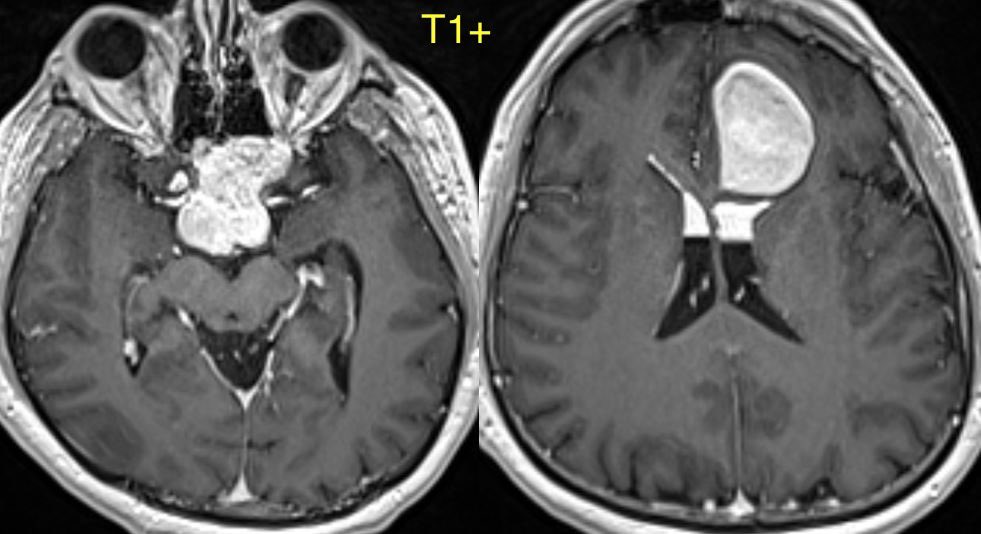

What is the most likely diagnosis in this 30 y/o patient with history of seizures presenting with severe headache?

More images in ๐Ÿงต

Additional images ๐Ÿ‘‡